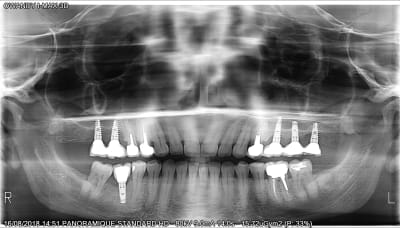

j'ai déjà déposé le secteur 1 mais je n'arrive pas a identifier les implants en 25 et 26?

il me semble que c'était les anciens safe shark implants qui étaient comme çà.... (enfin celui du milieu c'est un Zimmer....)